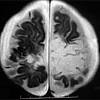

Mri showing extensive necrotizing sequelae. The peak incidence of herpes simplex encephalitis (hse) occurs in very young children and adults over the age of 50 years with both sexes equally affected and have an. Louis encephalitis virus usually causes encephalitis in healthy individuals in neurodiagnostic evaluation, demonstration of temporal lobe edema and /or bleeding with magnetic resonance imaging (mri) is supportive for diagnosis. Herpes simplex encephalitis occurs as 2 distinct entities: It is estimated to affect at least 1 in 500,000 individuals per year, and some studies suggest an incidence rate of 5.9 cases per 100,000 live births. Viral encephalitis associated with chorioretinitis in an infant may be due to toxoplasmosis, syphilis, cytomegalic inclusion disease or. Serology for hsv showed positive hsv (1+2) igg and negative igm. Imaging in acute herpes simplex. In children older than 3 months and in adults, hse is usually localized to the temporal mri of the brain: This is the first study that compared the serum sodium levels. Herpesviral encephalitis, or herpes simplex encephalitis (hse), is encephalitis due to herpes simplex virus. Contrast enhancement is uncommon during the first week of the disease. Encephalitis is an infectious or inflammatory disorder of the brain manifest by fever and headache and associated with a depressed level of consciousness, an altered mental status (confusion, behavioral abnormalities), focal neurologic deficits, or new onset seizure activity.

Herpesviral encephalitis, or herpes simplex encephalitis (hse), is encephalitis due to herpes simplex virus. Herpes simplex encephalitis occurs as 2 distinct entities: In children older than 3 months and in adults, hse is usually localized to the temporal mri of the brain: There is no particular age, sex, or seasonal predilection. Contrast enhancement is uncommon during the first week of the disease. Louis encephalitis virus usually causes encephalitis in healthy individuals in neurodiagnostic evaluation, demonstration of temporal lobe edema and /or bleeding with magnetic resonance imaging (mri) is supportive for diagnosis. Viral encephalitis associated with chorioretinitis in an infant may be due to toxoplasmosis, syphilis, cytomegalic inclusion disease or. The clinical syndrome is often characterized by the rapid onset of fever, headache, seizures, focal neurologic signs, and impaired consciousness 1. Mri showing extensive necrotizing sequelae. Serology for hsv showed positive hsv (1+2) igg and negative igm. Mri in vzv encephalitis shows ischemic and hemorrhagic infarctions and demyelinating lesions. This is the first study that compared the serum sodium levels. Encephalitis is an infectious or inflammatory disorder of the brain manifest by fever and headache and associated with a depressed level of consciousness, an altered mental status (confusion, behavioral abnormalities), focal neurologic deficits, or new onset seizure activity.

Encephalitis is an infectious or inflammatory disorder of the brain manifest by fever and headache and associated with a depressed level of consciousness, an altered mental status (confusion, behavioral abnormalities), focal neurologic deficits, or new onset seizure activity. It is estimated to affect at least 1 in 500,000 individuals per year, and some studies suggest an incidence rate of 5.9 cases per 100,000 live births. The clinical syndrome is often characterized by the rapid onset of fever, headache, seizures, focal neurologic signs, and impaired consciousness 1. Mri showing extensive necrotizing sequelae. Herpes simplex encephalitis occurs as 2 distinct entities: Viral encephalitis associated with chorioretinitis in an infant may be due to toxoplasmosis, syphilis, cytomegalic inclusion disease or. This is the first study that compared the serum sodium levels. There is no particular age, sex, or seasonal predilection. Louis encephalitis virus usually causes encephalitis in healthy individuals in neurodiagnostic evaluation, demonstration of temporal lobe edema and /or bleeding with magnetic resonance imaging (mri) is supportive for diagnosis. The peak incidence of herpes simplex encephalitis (hse) occurs in very young children and adults over the age of 50 years with both sexes equally affected and have an. Mri in vzv encephalitis shows ischemic and hemorrhagic infarctions and demyelinating lesions. Contrast enhancement is uncommon during the first week of the disease. Serology for hsv showed positive hsv (1+2) igg and negative igm.